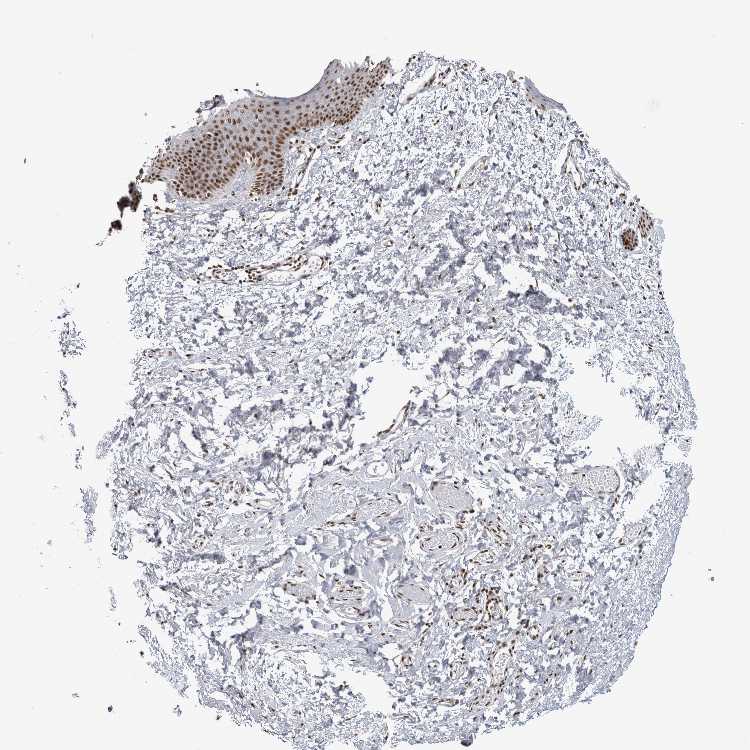

SKIN 1 - Antibody stainingi

Antibody staining in the annotated cell types in the current human tissue is reported as not detected, low, medium, or high, based on conventional immunohistochemistry profiling in selected tissues. This score is based on the combination of the staining intensity and fraction of stained cells.

Each image is clickable and will lead to virtual microscopy that enables deeper exploration of all samples and also displays staining intensity scores, fraction scores and subcellular localization as well as patient and tissue information for each sample.

Antibody HPA024331

Langerhans High

Fibroblasts High

Keratinocytes High

Melanocytes High